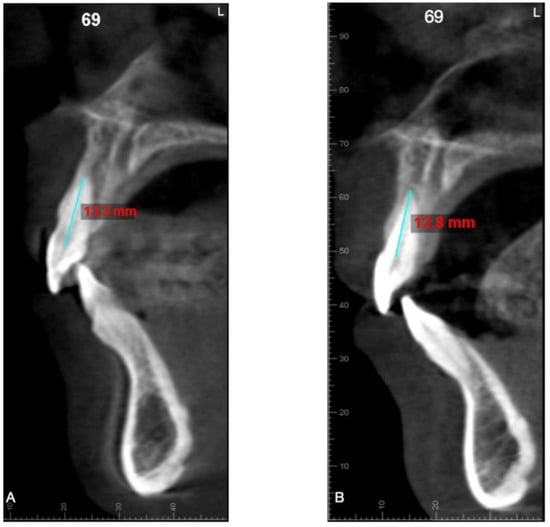

| Tooth | Changes in Root Length (mm) (Mean ± SD) | Range (mm) | Changes in Root Length (%) (Mean ± SD) | Range (%) | Tp | Confidence Interval | p-Value |

|---|---|---|---|---|---|---|---|

| Central incisor | −0.43 ± 0.27 | −1.10–0.10 | −3.27 ± 2.07 | −8.53–0.76 | 8.92 | 0.53–0.33 | * |

| Lateral incisor | −0.53 ± 0.38 | −1.50–0.10 | −4.03 ± 2.82 | −10.79–0.78 | 7.88 | 0.66–0.39 | * |

| Canine | −0.14 ± 0.13 | −0.60–0 | −0.83 ± 0.75 | −3.57–0 | 6.28 | 0.19–0.09 | * |

| First premolar | −0.08 ± 0.66 | −0.30–0 | −0.56 ± 0.42 | −2.20–0 | 8.31 | 0.11–0.10 | * |

| Second premolar | −0.003 ± 0.02 | −0.10–0 | −0.02 ± 0.13 | −0.70–0 | 1 | 0.004–0 | NS |

| First molar | −0.003 ± 0.01 | −0.10–0 | −0.02 ± 0.12 | −0.68–0 | 1 | 0.004–0 | NS |